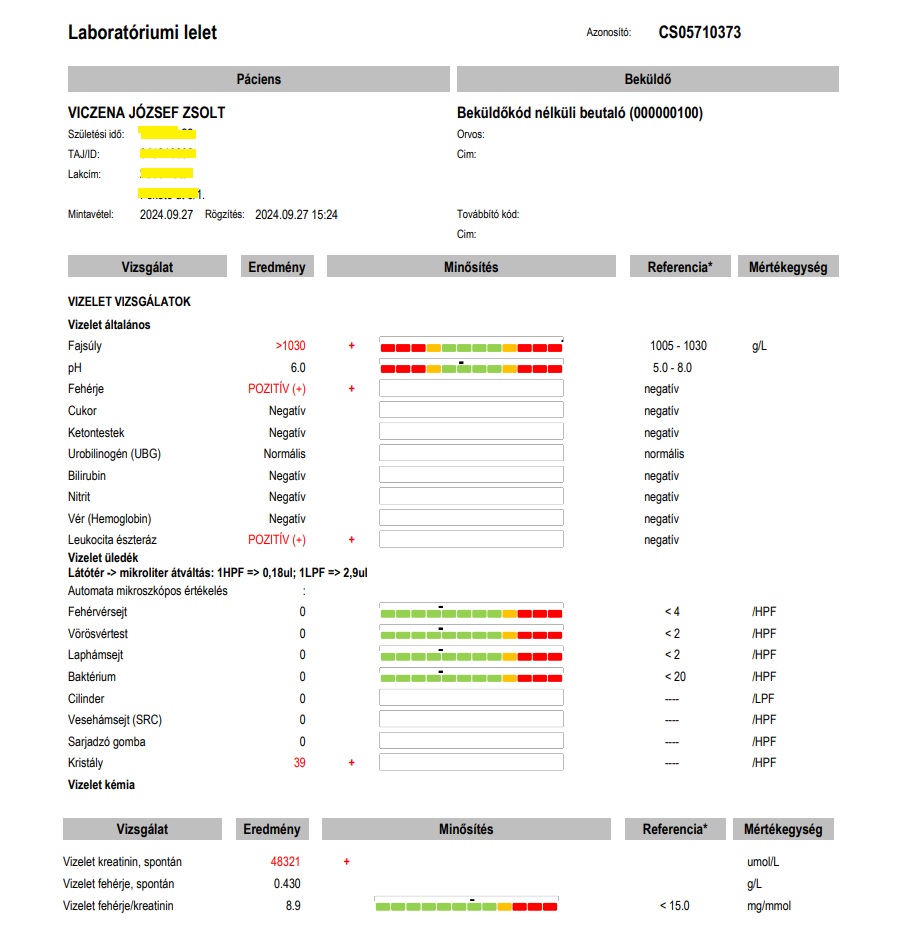

A 8. hónapban is, 2024 szeptemberében, fehérje van a vizeletben, leukocita észteráz pozitivitás (fertőzés megbízható jelzője), 4,5-szeres összefehérje érték a vizeletben, 3,5-szeres kreatinin érték a vizeletben (a vese „támadás”, „extrém terhelés” alatt van) – Az alábbi lelet ezt igazolja: